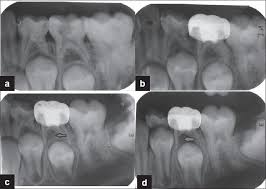

Types Of Dental X Rays Dental Hygiene School Dental Dental Hygiene Student